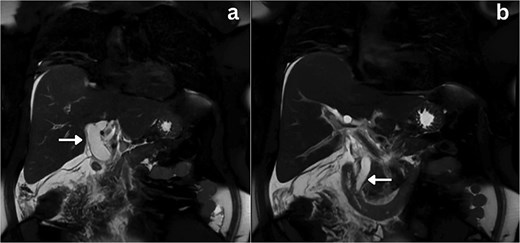

She was admitted, resuscitated, and started on intravenous antibiotics. Considering her previous history of cholecystectomy and deranged Liver Function Tests (LFTs), a clinical diagnosis of cholangitis was made. Magnetic retrograde cholangio-pancreatography (MRCP) was done, which showed significant dilatation of the biliary system extending down to the ampulla with the common hepatic duct (CHD) diameter of 23 mm with a normal pancreatic duct. Additionally, there was florid upper abdominal edema and fluid tracking along the right paracolic gutter (Fig. 1). There was no evidence of any common bile duct (CBD) stone or lesion to explain this dilatation. To further explore the underlying cause, a computed tomography (CT) pancreas was performed, which revealed no signs of pancreatitis nor any distal CBD or pancreatic lesions. The presence of fluid in the subhepatic and right paracolic regions likely indicated a bile leak (Fig. 2), but fluid related to pancreatitis could not be excluded. The findings were deliberated upon with the specialist hepatopancreaticobiliary (HPB) team and Specialist gastrointestinal (GI) radiologists. Despite extensive discussion and review with the radiologist, the nature of the fluid was not identified through the two imaging modalities employed. There was no obvious pancreatitis. A decision was reached to continue conservative management and opt for operative intervention in the event of clinical deterioration.

Axial section CT imaging; a) Normal pancreas with no evidence of inflammation or malignancy (arrow), b) extrahepatic biliary collection (asterisks).